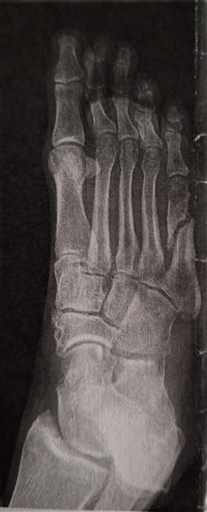

Röntgen

Torsdag 15 februari 2024 08:17

Fick bekräftat att jag bröt foten för 7v sedan.

Fortfarande inte läkt men sjukvården gör inget och de tror att det borde vara läkt om 4-5v.

Milano marathon om 7v känns lite tveksamt.